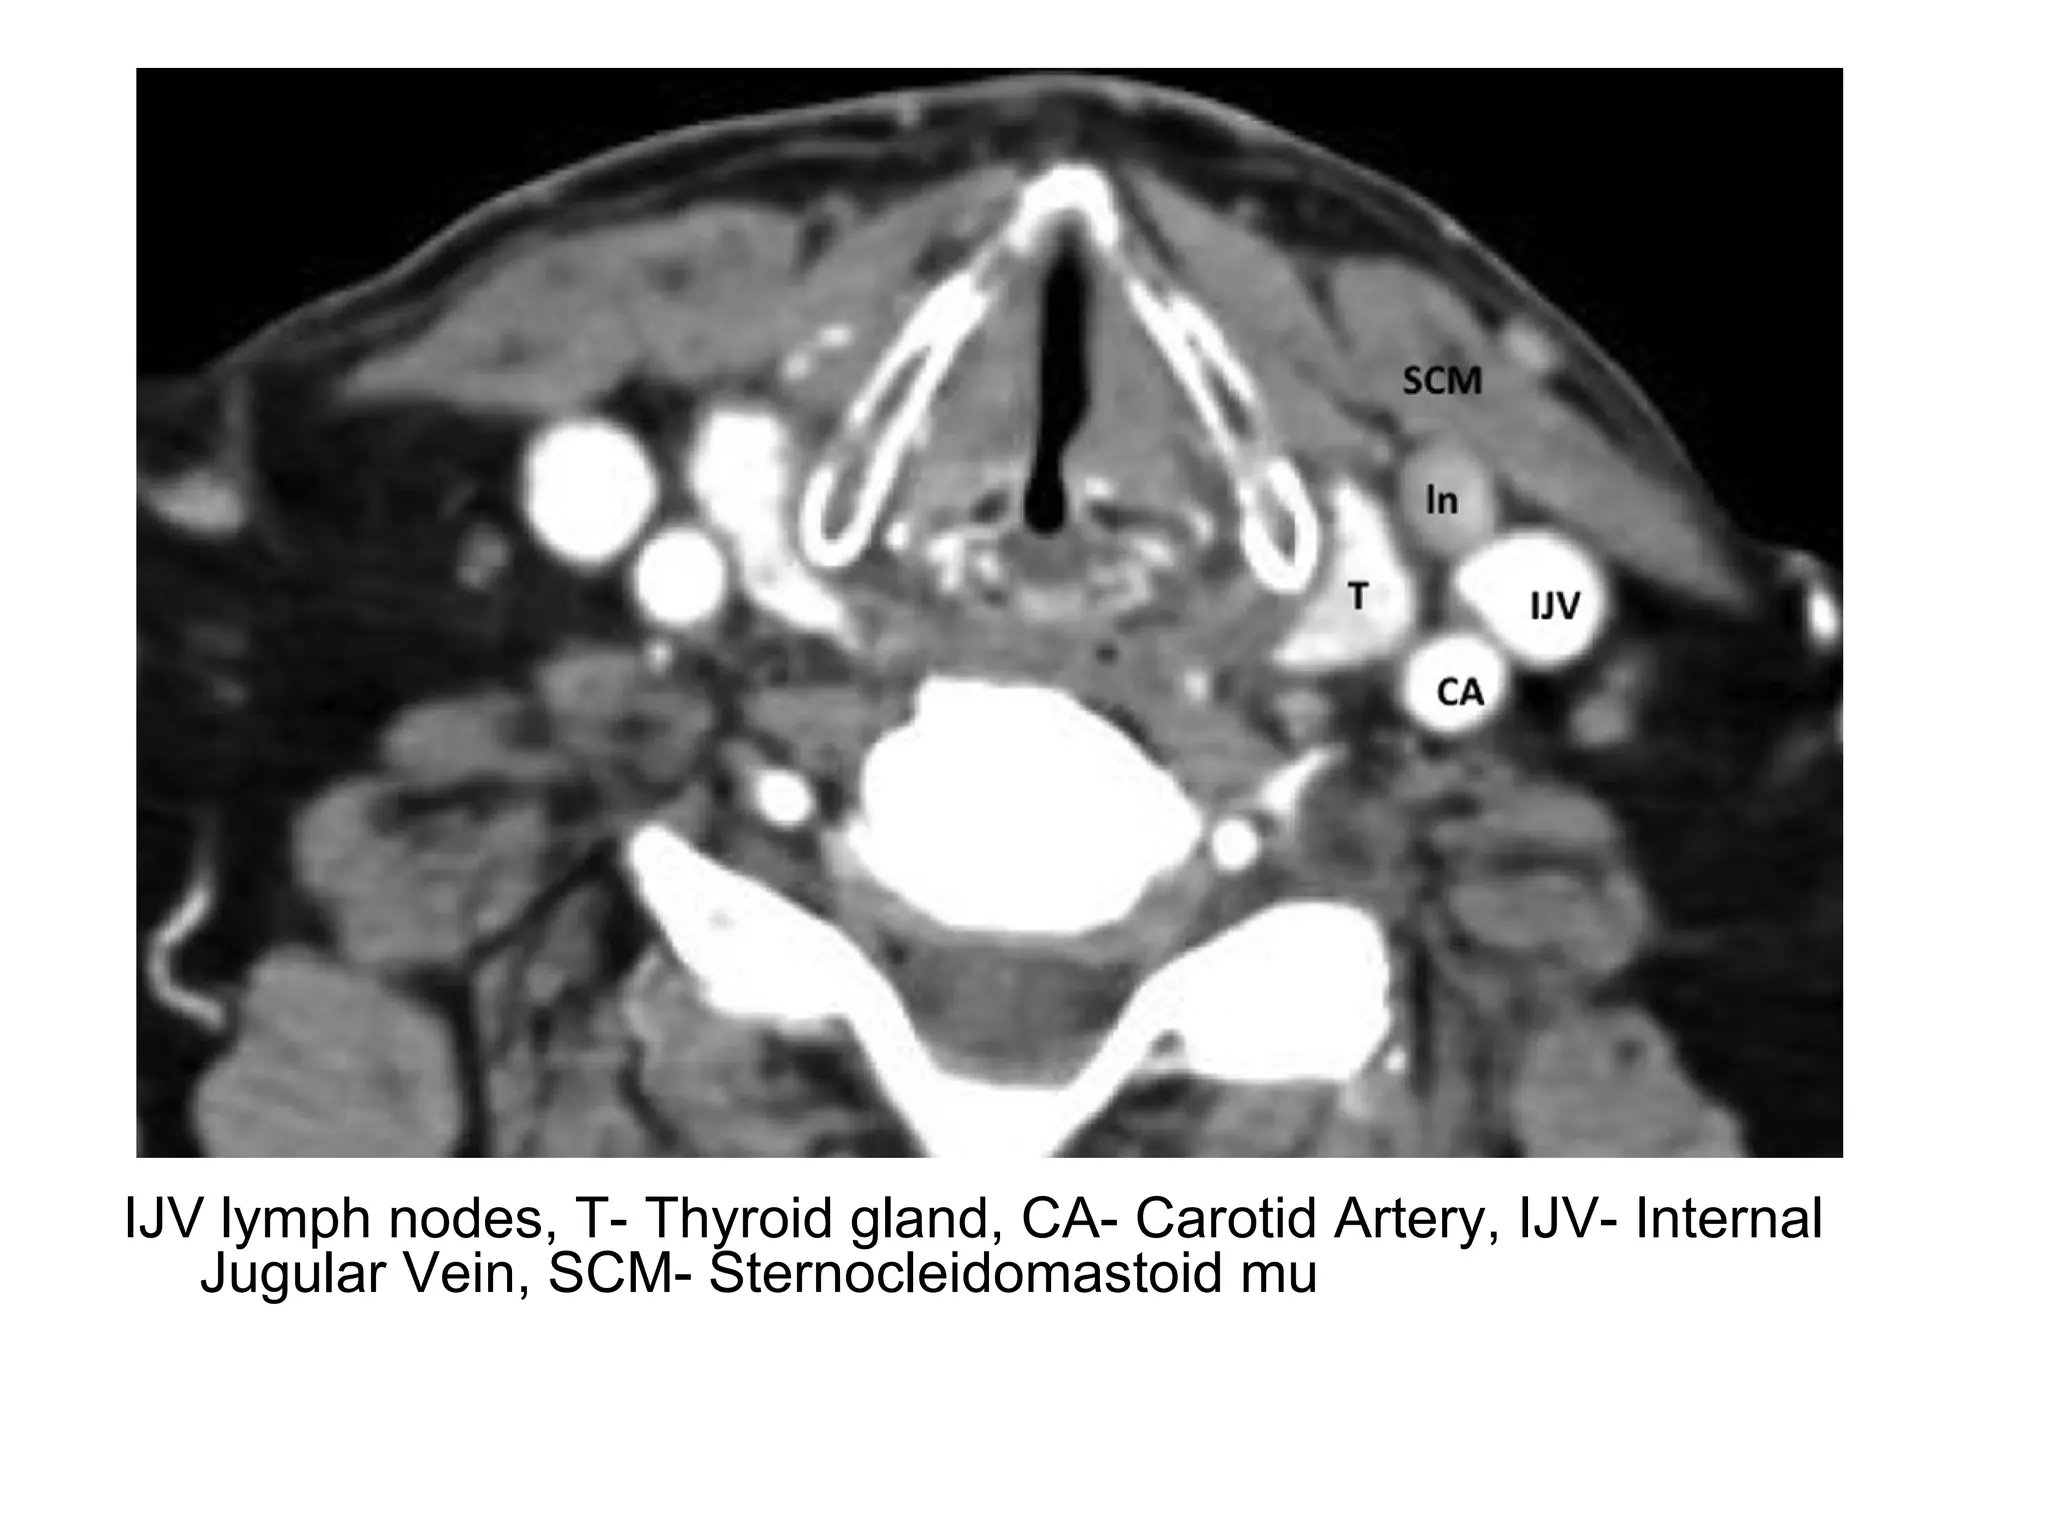

IJV lymph nodes, T- Thyroid gland, CA- Carotid Artery, IJV- Internal

Jugular Vein, SCM- Sternocleidomastoid mu

IJV lymph nodes,T- Thyroid gland, CA- Carotid Artery, IJV- Internal Jugular Vein, SCM- Sternocleidomastoid mu